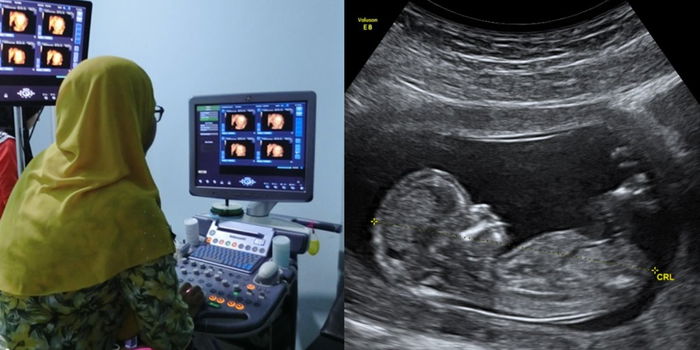

Masalah buah pinggang bengkak atau Hidronefrosis dapat dikesan lebih awal melalui details scan. Rawatan lebih lanjut dapat dilakukan selepas bayi dilahirkan

Ibu mengandung digalakkan untuk melakukan details scan bagi memeriksa bahagian organ bayi secara lebih terperinci, jantina bayi, jumlah air ketuban, kedudukan uri, masalah buah pinggang dan lain-lain lagi. Masa yang paling sesuai adalah ketika kandungan berada 18 hingga 24 minggu.

Melalui perkembangan teknologi ultrasound, hidronefrosis kini boleh dikesan semasa dalam kandungan dan rawatan selepas kelahiran bayi dapat dirancang secara lebih awal.

Ibu-ibu mengandung dinasihatkan untuk membuat ujian ultrasound semasa kehamilan yang terperinci ketika trimester kedua bagi mengetahui tahap perkembangan struktur saluran kencing dan buah pinggang anak dalam kandungan.

Kesimpulannya sangat penting untuk para ibu membuat details scan bagi memastikan keadaan bayi dalam kandungan adalah baik. Jika terdapat masalah sebegini, ibu ayah dan doktor dapat bersedia lebih awal.